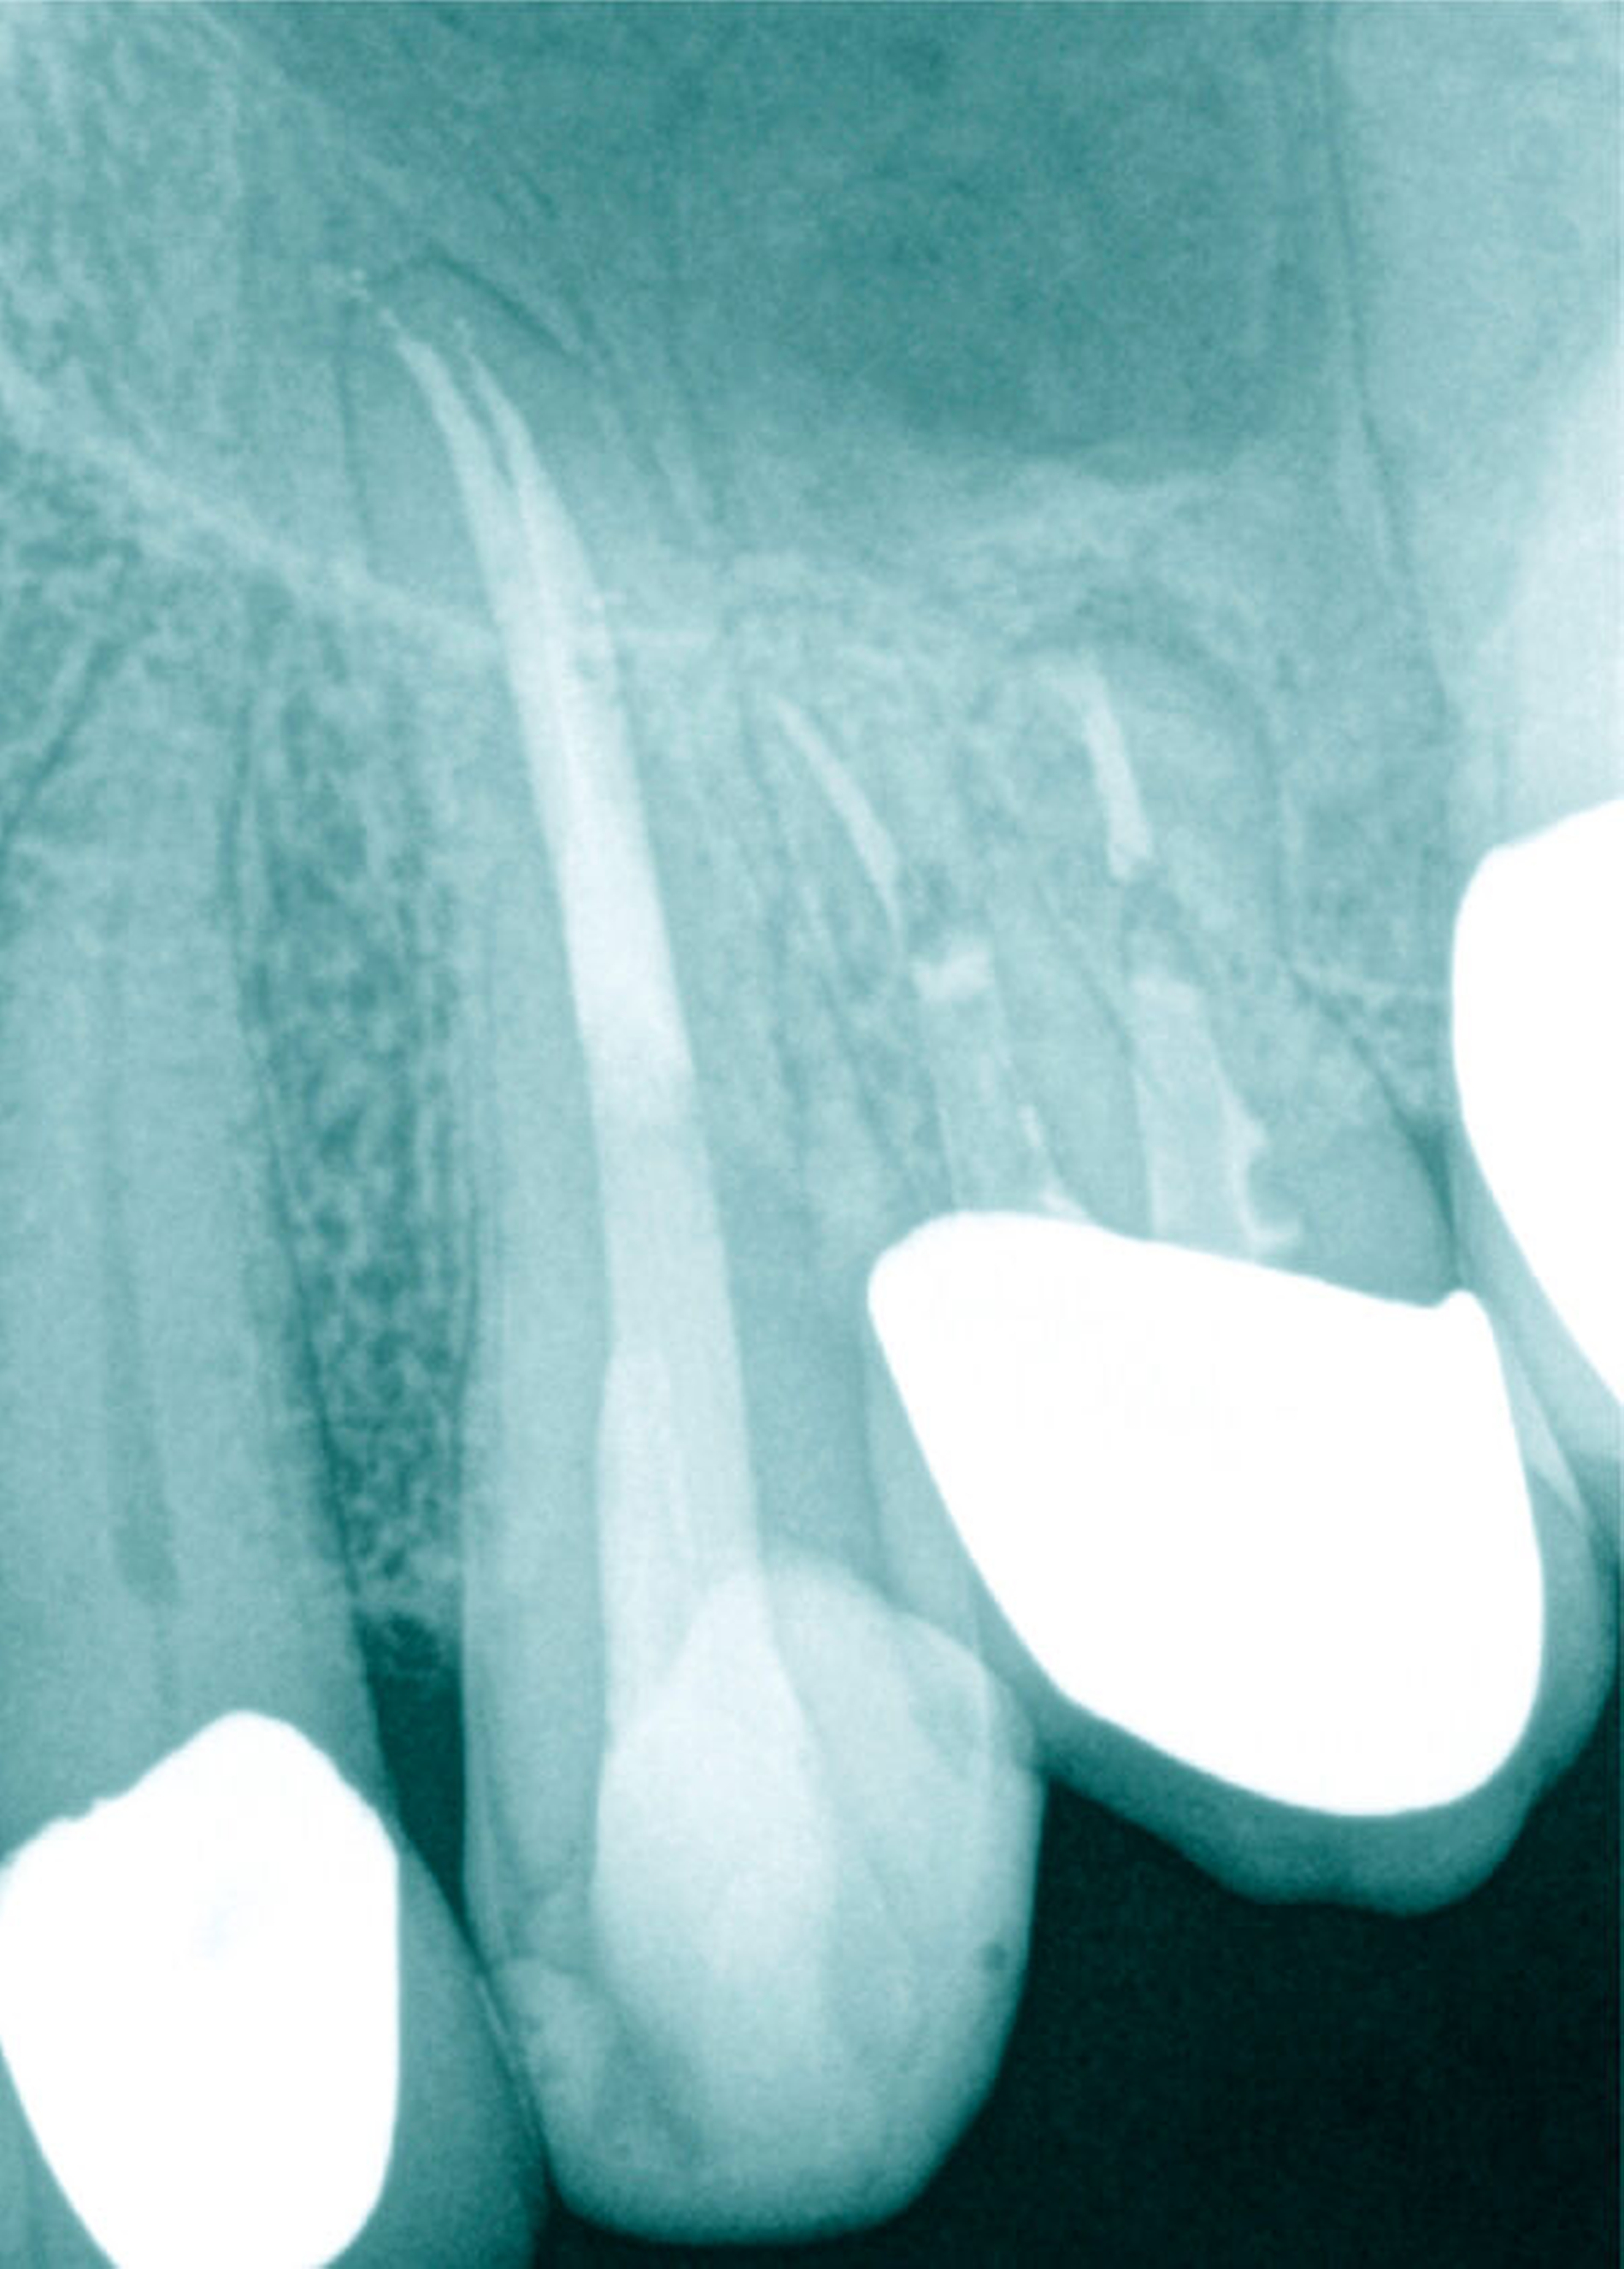

Apikal kann die Wurzel einen geraden Verlauf einnehmen, der Wurzelkanal aber innerhalb der geraden Wurzel stark gekrümmt verlaufen. Insbesondere auf rechtwinkligen intraoralen Röntgenaufnahmen kann die apikale Krümmung eines Wurzelkanals projektionsbedingt nicht exakt abgebildet werden.

Von klinischer Bedeutung sind bei seitlichen Schneidezähnen (und Eckzähnen) mehrere anatomische Besonderheiten. So können die nach distal gerichteten apikalen Krümmungen eine vollständige Erweiterung und Desinfektion erschweren. Die apikale Begradigung und Verlagerung des apikalen Foramens mit iatrogener Vergrößerung, die Verblockung mit Debris oder die Fraktur von Wurzelkanalinstrumenten sind keine seltenen Komplikationen – sie können das Ergebnis der Wurzelkanalbehandlung negativ beeinflussen (Abbildung 12).